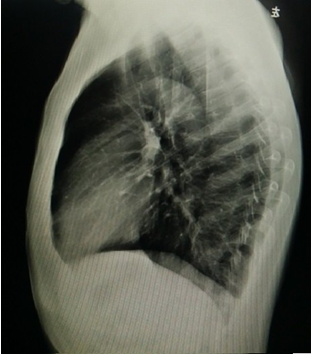

COPD的病理改變主要表現(xiàn)為慢性支氣管炎及肺氣腫的病理變化。

【桶狀胸、過清音】